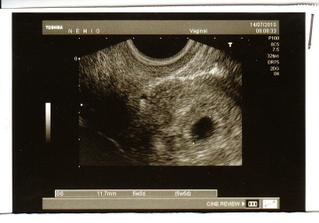

14.7. první UTZ, moc toho vidět není, jen gestační váček. Jsme 5+0